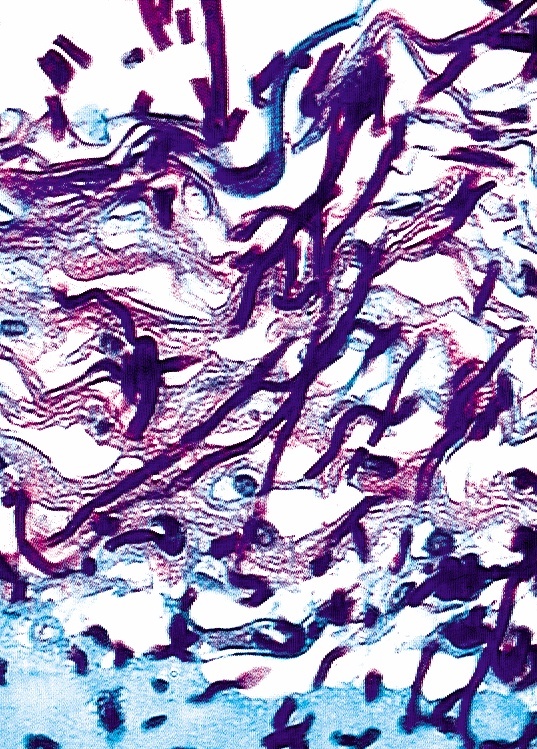

Die so entstehenden Stämme, denen genau ein Protein fehlt, können in Studien mit Mäusen auf ihre Virulenz überprüft werden. Ein Nachteil hierbei ist jedoch, dass Mäuse in der Natur nicht von Candida-Zellen befallen werden und es unklar ist, inwieweit die Ergebnisse auf den Menschen übertragen werden können. In hausinterner Zusammenarbeit mit der Abteilung "Zellsysteme" entwickelten die Forscher daher ein Modell-system der menschlichen Haut, das es ermöglicht, Infektionsvorgänge von Krankheitserregern zu verfolgen und zu untersuchen. Das Modell wird aufgebaut aus dermalen Fibroblasten, die - eingebettet in eine Biomatrix aus gewebetypischen Matrixproteinen - die Grundlage für die darauf ausgesäten Keratinozyten bilden. Nach mehrwöchiger Kulturdauer differenzieren die Keratinozyten zu einer mehrschichtigen Epidermis mit abschlie-ßender Hornschicht (Stratum corneum). Das Modell weist organspezifische Eigenschaften auf und eignet sich zur Erforschung von Erkrankun-gen, die durch Mikroorganismen wie Pilze und Bakterien und sogar Viren und Parasiten hervorgerufen werden. Auch ein Modellsystem des menschlichen Dickdarms, bestehend aus humanen, malignen Enterozyten und Fibroblasten, haben die Forscher bereits entwickelt. Während sich das Hautmodell besser für Invasionsstudien eignet, können mit dem Darmmodell insbesondere Adhäsionsvorgänge untersucht werden. "Wir haben mit Hilfe dieser in-vitro-Assays Proteine identifiziert, die für die Hyphenbildung von Candida albicans und die Infektion des Gewebes notwendig sind", sagt Wissenschaftler Rupp. Die Hyphen ermöglichen dem Pilz, in Organe einzuwandern und aus Immunzellen zu entkommen. "Die an der Hyphenbildung beteiligten Proteine sind für die Pathogenität des Pilzes essenziell und somit ideale Zielmoleküle für eine medikamentöse Blockierung", so Rupp.

Die in-vitro-Modelle erlauben Einblicke in zentrale Mechanismen der Virulenz, die mit Tierversuchen nur schwer erzielt werden können: So kann die Adhäsion der Erreger an die Wirtszellen und die anschließende Invasion oder Penetration der Zellen genau verfolgt werden - also die Rolle einzelner Proteine bei der Infektion bestimmt werden. "Die Modelle ergänzen so Tierversuche oder helfen, sie zu vermeiden. Darüber hinaus können sie auch für die Wirkstoffsuche eingesetzt werden" sagt Hans-Georg Eckert, Leiter der Abteilung "Zellsysteme". Derzeit entwickeln die Forscher ein Hautmodell für die Krebsforschung, mit dem z. B. der Einfluss von Wachstumsfaktoren auf das Invasionsverhalten von Hauttumoren oder die Wirksamkeit möglicher Tumortherapeutika untersucht werden können.